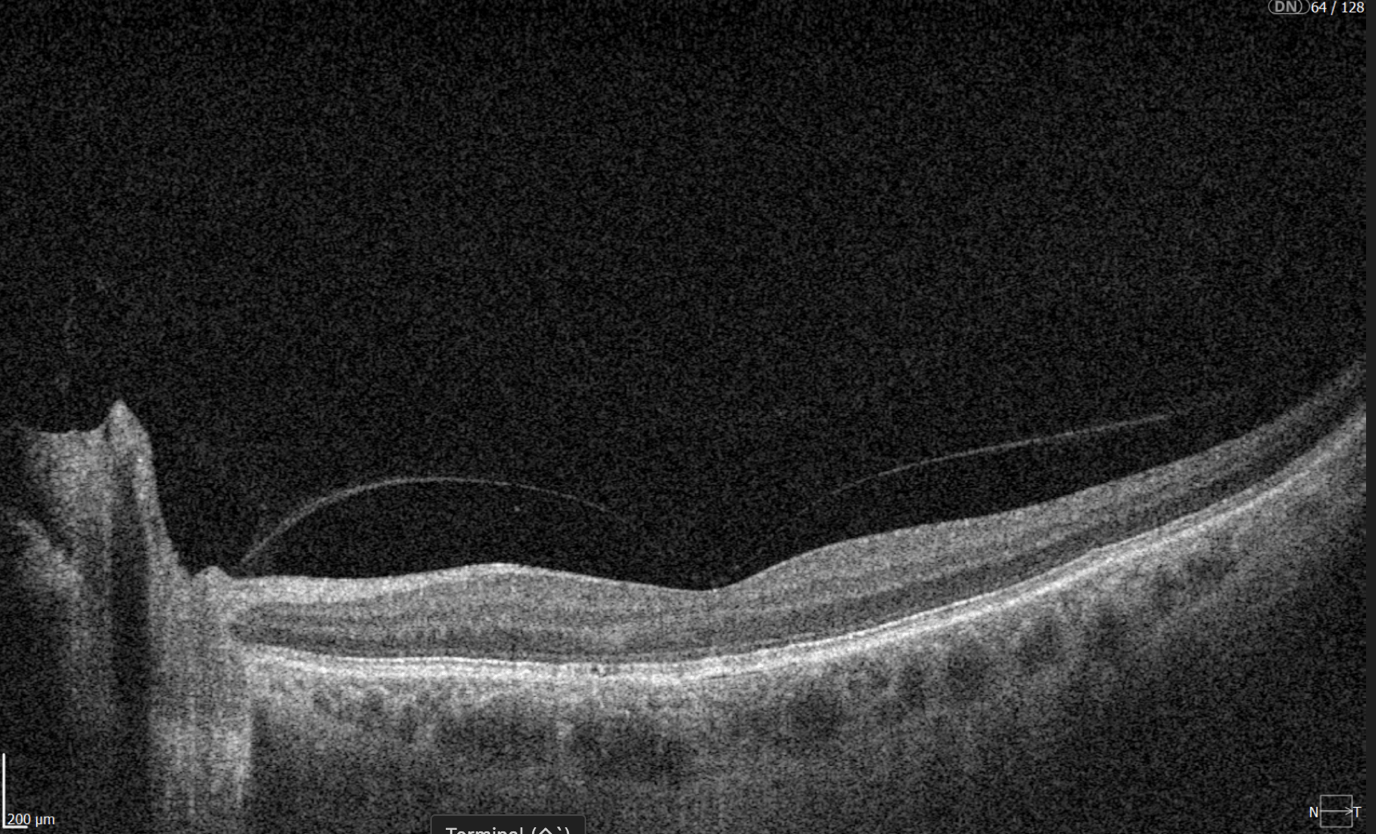

New Tech in Optometry: New Iterations of OCT

Even though OCTs entered the market relatively recently, they swiftly became indispensable ancillary tests in ophthalmic practice for many professionals. The primary reason is their high-quality imaging of the retina, nerve fiber layer, and optic nerve, offering a near in-vivo “optical biopsy” of the retina.

However, the technology continues to evolve – partly due to technological advancements and partly due to the ability to extract even more data from OCT machines through sophisticated software.

En-face OCT in current systems is based on software reconstruction of OCT images. Image slices are selected retrospectively from full recorded volumes or calculated by depth projection along specific depth ranges, enabling three-dimensional data visualization in a fundus projection. This technique allows the projection of specific retinal and/or choroidal layers at a given depth onto an en-face view.

While we are more accustomed to working with cross-sectional images (B-scans), microstructural changes and the retinal and choroidal vasculature morphology are challenging to evaluate using B-scans alone. En-face OCT offers numerous advantages, including the ability to precisely localize lesions within specific subretinal layers using their axial location on OCT cross-sections and to register projected OCT images to other fundus imaging modalities using retinal vessels as landmarks.

Currently, en-face OCT is being applied to various specialized areas within the eye, encompassing the anterior segment, glaucoma, infectious diseases, and the retina.

Optometry Technology: SS-OCT

Like SD-OCT, swept-source OCT (SS-OCT) utilizes Fourier domain technology to optimize higher-quality wavelength transduction within the frequency domain. This enables rapid sweeping scan patterns across a broad bandwidth.

However, instead of a broad-bandwidth light source projected all at once, as in SD-OCT, SS-OCT employs a single tunable laser that sweeps through different frequencies to cover the entire spectrum swiftly. The light reflected from the eye is captured by a photodetector significantly faster than the charge-coupled device (CCD) camera used in SD-OCTs. This difference translates to a faster scanning speed of up to 400,000 axial scans per second, eliminating the typical depth-dependent signal drop-off associated with SD-OCT. Additionally, the faster scanning speed reduces image distortions caused by eye movements and allows for wider B-scans, facilitating widefield imaging.

Furthermore, many SS-OCT systems utilize a light source centered at an approximately 1050 nm wavelength, providing better tissue penetration than SD-OCT. This allows for visualization of structures like the choroid, lamina cribrosa, and structures at the anterior chamber angle. This enhanced penetration is crucial in diseases like Central Serous Chorioretinopathy, where evaluating the entire thickness of the choroid can be challenging.

Moreover, volumetric analysis of the choroid and various pathological features can aid in monitoring the progression of Wet AMD, CSCR, and Diabetic Retinopathy, as well as assessing the response to treatments such as anti-VEGF agents, laser photocoagulation, and photodynamic therapy (PDT).

Wide-Field and Ultrawide-Field OCT (WF-OCT and UWF-OCT)

While OCT is a powerful ocular imaging tool, it has traditionally been limited by a relatively narrow field of view (FOV) – typically around 20 degrees × 20 degrees. To address this limitation, two advancements have emerged:

- Wide-field OCT (WF-OCT) with an FOV of approximately 60-100 degrees captures the retina’s mid-periphery up to the posterior edge of the vortex vein ampulla.

- Ultrawide-field OCT (UWF-OCT) with an FOV of up to 200 degrees, mapping the far periphery of the retina, including the anterior edge of the vortex vein ampulla and beyond.

WF-OCT provides additional information compared to routine 6-9 mm scans in conditions such as diabetic retinopathy (DR), central serous chorioretinopathy (CSCR), polypoidal choroidal vasculopathy (PCV), peripapillary choroidal neovascular membrane (CNVM), or uveitic entities. It facilitates easier visualization of anatomical details of peripheral retinal changes like ischemic areas in DR, retinal vein occlusions, or sites of retinal breaks, peripheral retinal detachment, retinoschisis, and choroidal lesions (melanoma, nevus, hemangioma, choroidal metastasis).

As with other OCT iterations, WF and UWF OCT will likely provide the most significant insights when routinely combined with other modalities, such as OCT angiography.